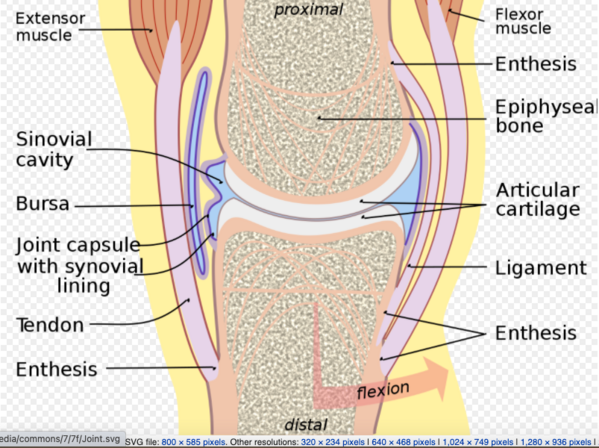

Synovial joints are the most common type of joint in the body . These joints are diarthrodial, meaning they are freely mobile.

A characteristic for a synovial joint that is not seen at fibrous or cartilaginous joints is the presence of a joint cavity. The joint cavity contains synovial fluid, secreted by the synovial membrane (synovium), hich lines the articular capsule. The articulating surfaces of the bones contact each other in this fluid-filled space. Hyaline cartilage forms the articular cartilage, covering the entire articulating surface of each bone.

A few synovial joints of the body have a fibrocartilage structure located between the articulating bones. This is called an articular disc, which is generally small and oval-shaped, or a meniscus, which is larger and C-shaped. Synovial joints are further classified based on the type of movements they allow.

The bones in a synovial joint are connected by ligaments.

Ligaments are a type of tough, fibrous and elastic connective tissue. Ligaments appear as crisscross bands that attach bone to bone and help stabilize joints.

The movement at a synovial joint is caused by the muscles attached across the joint. Muscles are attached to bone by tendons. Tendons are very strong, inelastic connective tissues that allow a muscle to pull on a bone to move it. Tendons are found throughout the body, from the head down to the feet. The Achilles tendon is the largest tendon in the body. It attaches the calf muscle to the heel bone.